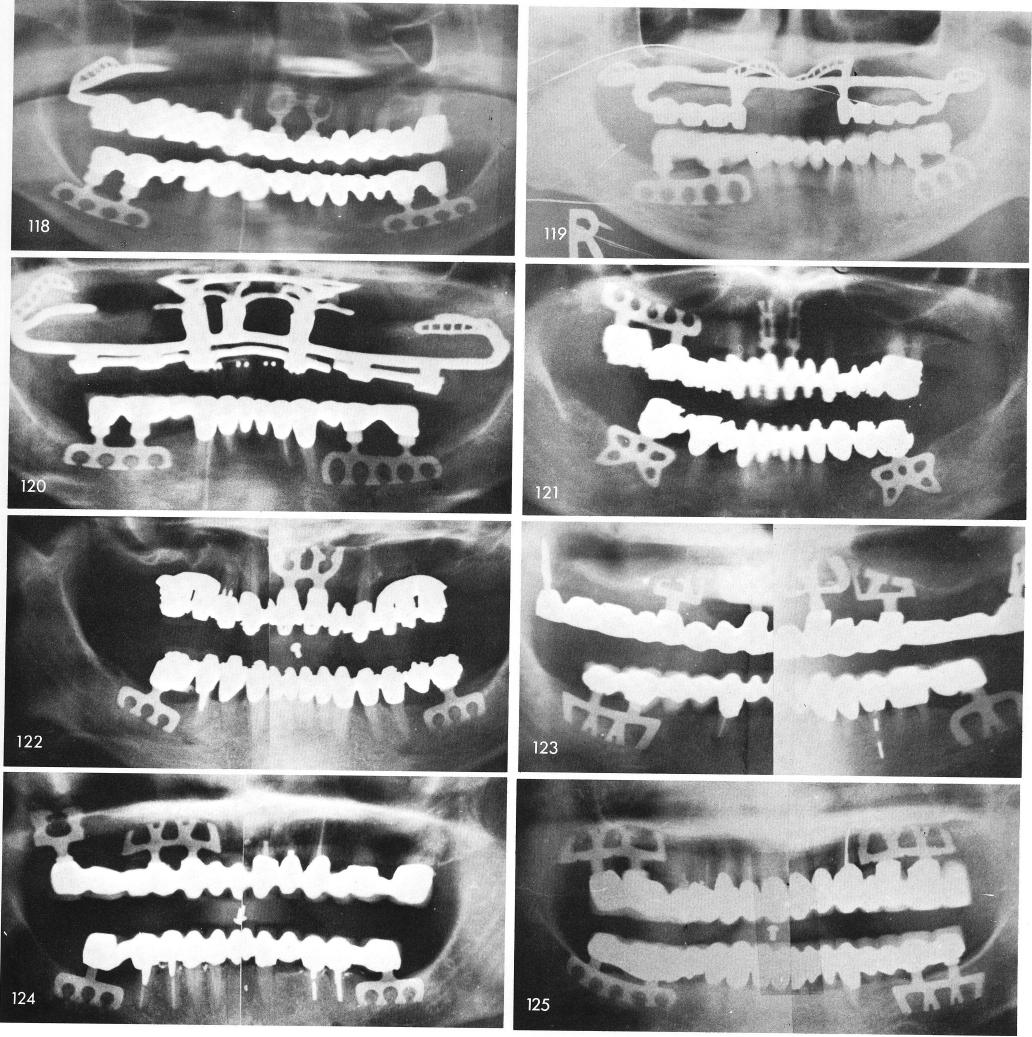

Mandibular Implants (published 1977)   Dr. Leonard I. Linkow